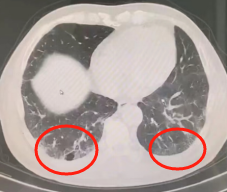

▲2023年胸部CT显示,双肺间质性肺炎

(画圈处)病变较前增多、进展